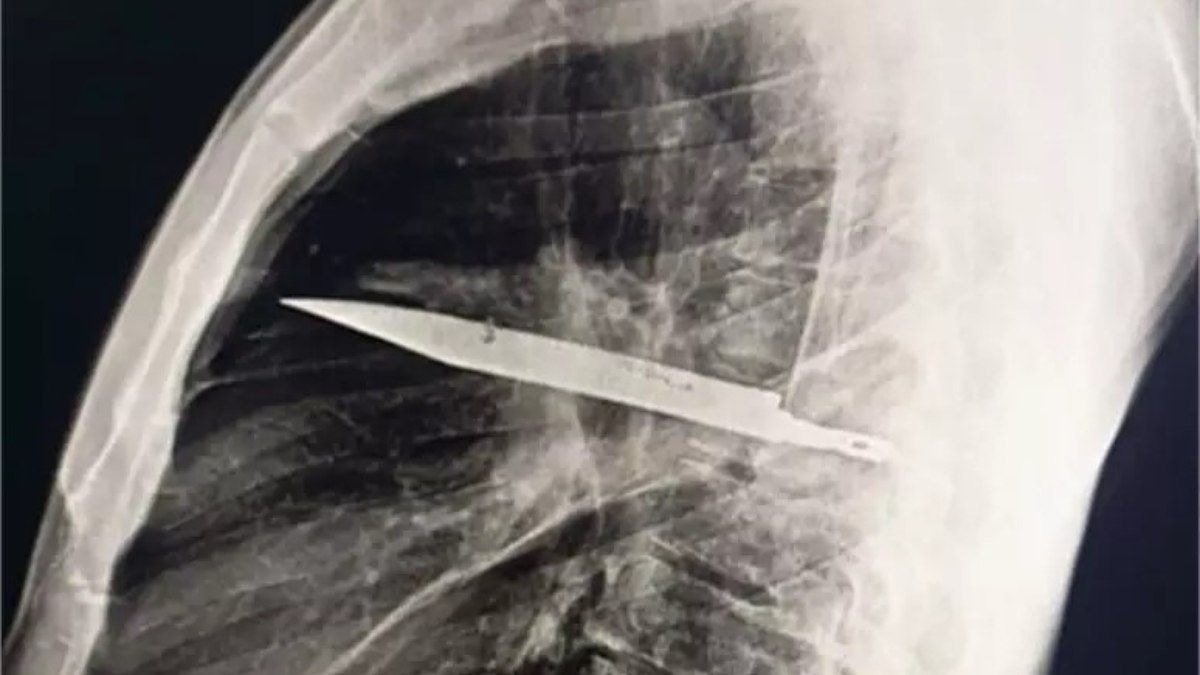

Um homem de 44 anos ficou surpreso ao descobrir que vivia com uma faca alojada no peito há oito anos. Este caso curioso ocorreu na Tanzânia, quando o paciente procurou atendimento médico devido à secreção notada abaixo do mamilo. A situação foi investigada pelo médico que o atendeu no Hospital Nacional de Muhimbili.

Na época, o paciente recebeu pontos nas áreas feridas e se recuperou sem complicações aparentes. No entanto, a situação mudou quando ele, após anos, notou a secreção e decidiu investigar. Após o relato, o médico pediu uma radiografia, que revelou a lâmina da faca atravessada no tórax, mas felizmente não atingindo órgãos vitais.

Os médicos explicaram que o acúmulo de pus observado era resultado da presença do corpo estranho e do tecido danificado ao redor. O caso, que chamou a atenção da comunidade médica, foi publicado no Journal of Surgical Case Reports, evidenciando a raridade de uma faca alojada no corpo por tanto tempo.